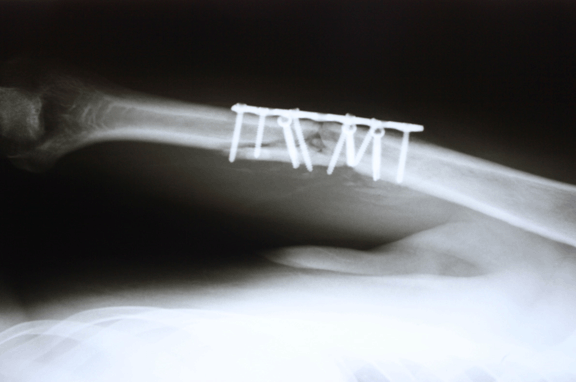

A 28-year-old male diagnosed with closed humerus shaft fracture due traffic accident without neurovascular injury. He was treated with open reduction and plate fixation at another hospital four months ago. (Figure 1A-B) Postoperative period was uneventful. However, there was a lack of union after 12 weeks. (Figure 2) He was presented to our outpatient clinic with severe pain after a minor trauma. The plain radiographs revealed a non-union of humerus shaft fracture with loss of reduction and implant failure with a broken screw. (Figure 3) There was no evidence of infection on clinical examination and C-reactive protein level was also normal. The patient was diagnosed with atrophic non-union with implant failure and offered revision surgery with implant removal, bone grafting and fixation with a longer and thicker plate. However, the patient did not accept revision surgery demanded conservative treatment. Closed manipulation (Figure 4A-B) under sedation and a Sarmiento type brace cast was applied. Although the reduction was good, the patient was informed of high risk of ineffectiveness of this treatment method. During monthly follow-up, there was no loss of reduction again, and at the fourth month follow-up after closed manipulation solid bony union was achieved without any deformity. (Figure 5A-B)

Figure 3: Implant failure with loss of reduction and broken screw.

Figure 4: (A, B) Implant after close reduction.